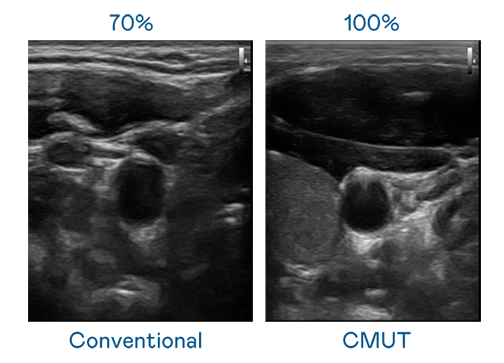

CMUT 技术是一种用电容式微机电元件来产生超音波讯号的技术。与传统 PZT 压电式技术相比,CMUT 频宽增加 30%,更宽频的超音波讯号让影像解析度大幅提升,是实现高影像品质医疗超音波扫描、促进精准医疗发展的关键技术。

大频宽带来超清晰影像

超音波影像的解析度高低,首先取决于探头能发出的讯号频宽。尊龙时凯 CMUT 可提供高清晰的超音波讯号,提供高频宽、高灵敏度、影像纹理细节更高的超音波影像,协助医护人员缩短影像判读时间及利用精准的医疗影像进行诊断。